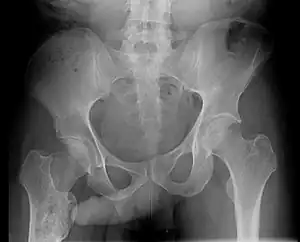

The John Thomas sign,[1] also known as the Throckmorton sign,[2] is a slang or joke term used in the field of radiology. It refers to the position of a penis as it relates to pathology on an X-ray of a pelvis. When the penis (visible on the X-ray as a shadow) points towards the same side as a unilateral medical condition such as a broken bone, this is considered a "positive John Thomas sign," and if the shadow points to the other side, it is a "negative John Thomas sign."[3]

Studies have shown that the "sign" is no better than chance at identifying the location of a hip fracture.[4][5] In those cases where the John Thomas sign is positive, it has been proposed that a person with a displaced hip fracture may try to lie on the injured side to immobilize the fracture and reduce pain; the penis then inclines toward the downward (injured) side.[6]

Andy Murray, British professional tennis player, released a picture of his pelvic X-ray following his hip resurfacing surgery on January 29, 2019[7] clearly demonstrating an example of a negative John Thomas or Throckmorton sign where his penis pointed away from the site of injury. The release of the X-ray image with visible genitalia was discussed by Piers Morgan on Good Morning Britain, prompting Murray, who was watching at the time, to message the show, stating, "Please can you stop discussing my genitals on national TV, I was heavily medicated at the time of posting."[8]